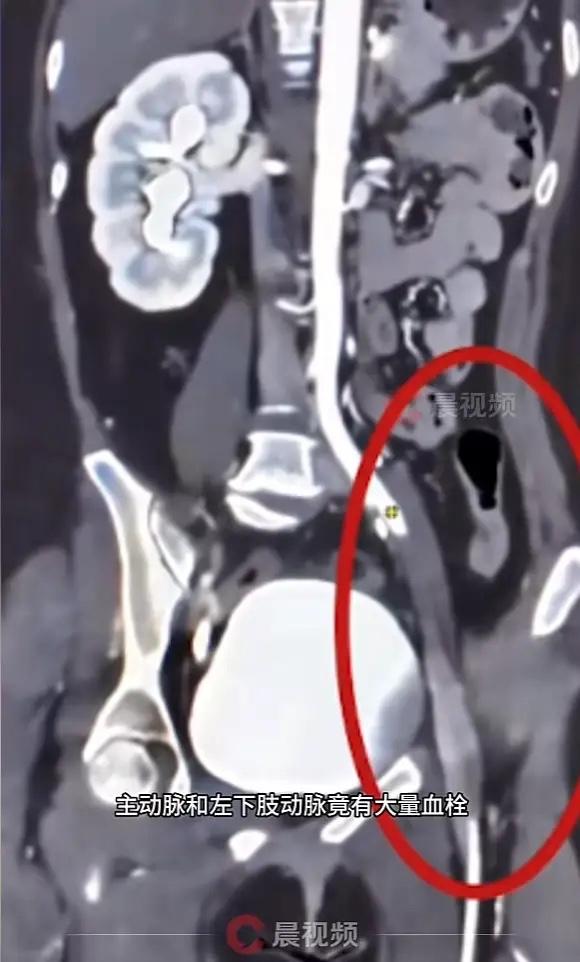

江苏南京,一女子为了祛痘,听信偏方,自行服用了一个多月的短效避孕药,没想到左腿突然麻木剧痛,送医后竟被查出主动脉和左下肢动脉大量血栓,不仅可能截肢,还有生命危险!网友:还敢乱吃药吗? 南京的陆女士怎么也没想到,几颗痘痘竟让她在鬼门关前走了一遭。她轻信了网络上的“美容偏方”,连续一个多月自行服用短效避孕药,以为能调理激素、祛痘美容。 那天她下楼倒垃圾时,左腿突然变得无力、发麻、冰凉,还伴着剧烈疼痛,起初她以为是劳累所致,休息一下就能缓解。然而症状反复出现,甚至在出差途中急剧加重,左腿皮肤变得苍白。她这才意识到问题严重,紧急返回南京就医。 检查结果她的主动脉和左下肢动脉形成了大量血栓,下肢动脉完全堵塞,左腿供血中断。医生说,再晚来一步,不仅腿保不住,生命都可能受到巨大威胁。 医护人员为她进行了紧急手术,开通了主要血管,但危险并未就此解除。由于她的血液一直处于高凝状态,术后双腿和左肾动脉又出现了新的血栓,不得不进行第二次血栓清除手术。严重的并发症接连出现,糖尿病、酮症酸中毒、低蛋白血症都来了,她的心率持续居高不下,最终被送进了ICU和CCU接受24小时监护。 短效避孕药中含有的雌激素成分,会增加血液黏稠度,从而诱发血栓风险。对某些有高危因素的人来说,自行服药无疑是在冒险。避孕药引起的血栓可能发生在全身多个部位。除了像陆女士这样的下肢动脉,还可能引发脑静脉窦血栓或肺栓塞,每一种都可能致命。 经过医护人员全力以赴的救治,陆女士最终逐渐好转,脱离了生命危险。但这段经历给她留下了深刻的教训。她后悔当初没有咨询专业医生,轻信了网络偏方。 药品不是普通的消费品,任何药物都应在医生或药师的指导下使用。在追求美丽的道路上,健康永远应该是第一位的。 各位读者你们怎么看?欢迎在评论区讨论。